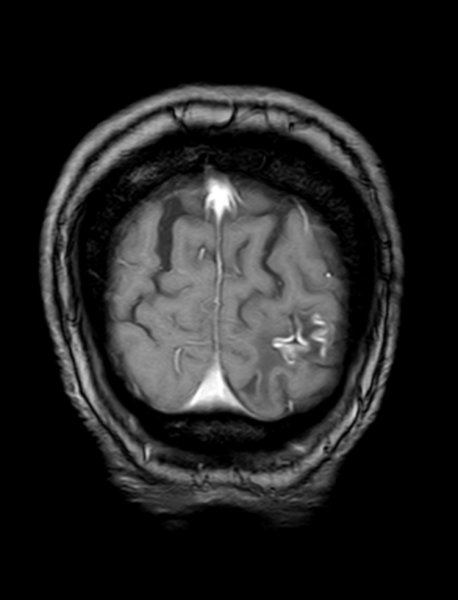

Posteriorinfarkt

Posteriorinfarkt Flair Sensitiv - axial